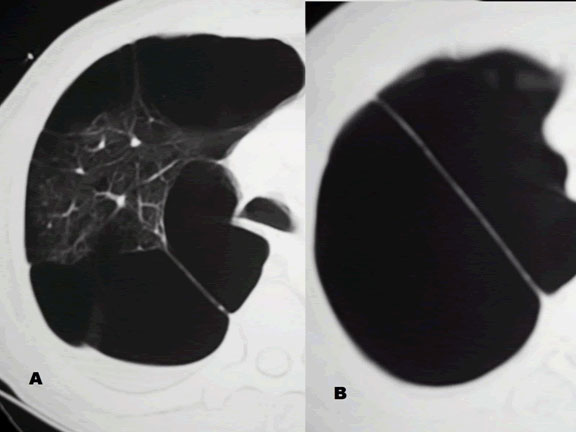

| Figure 2. Right hemithorax with smaller bullae |

The patient was afebrile and hemodynamically stable. However, pulse oximetry registered 70% as the patient was receiving 4 liters of oxygen by nasal canula. On physical examination, the patient had diminished breath sounds in the right-upper chest and diffuse expiratory wheezing. An arterial blood gas (ABG) in the ED revealed a pH 7.23, PaCO2 126 mm Hg, PaO2 37 mm Hg and SaO2 72%. An admission chest roentogram was obtained and revealed a large right-upper lobe lucency without evidence of pneumothorax (Figure 1). The patient was endotracheally intubated in the ED for respiratory distress, and a repeat ABG (pH 7.39, PaCO2 83 mm Hg, PaO2 160 mm Hg and SaO2 92%) on ventilator settings of tidal volume 500 ml, no positive end-expiratory pressure, respiratory rate of 20 breaths per minute and 50% FiO2 showed improvement. Following intubation, the patient was admitted to the MICU and aggressive pulmonary therapy was pursued. Intravenous steroids, frequent nebulizers and intravenous antibiotics were also administered. Chest computed tomography (CT) demonstrated a massive right apical bulla occupying nearly one-third of the right hemithorax along with several smaller bullae seen throughout the right and left lungs (Figure 2). The patient subsequently improved, and was able to be extubated on the morning of the second hospital day. A post-extubation ABG on 2 liters of oxygen by nasal canula was pH 7.36, PaCO2 85 mm Hg, PaO2 55 mm Hg and SaO2 85%. Pulmonary function tests (PFTs) revealed an FEV1 of 0.39 liters (9% of predicted) and a FVC of 0.8 liters (16% of predicted).

The patient returned to his baseline pulmonary status following continued medical and pulmonary therapy. It was apparent that the giant right-upper lobe bulla was causing compression of his pulmonary parenchyma and interfering with his pulmonary mechanics. Therefore, the patient electively underwent right thoractomy and stapling resection of the right-upper lobe bulla (Figure 3). There were several smaller bullae distributed in the remaining lung tissue, and these were not resected due to their diffuse nature. The resected specimen measured 9.5 cm x 5.5 cm x 4.0 cm, and represented benign lung tissue on pathologic examination (Figure 4). The patient had an uneventful post-operative recovery, and was discharged home on 2 liters nasal canula. Subsequently, he was able to be weaned-off home oxygen and his exercise tolerance improved.